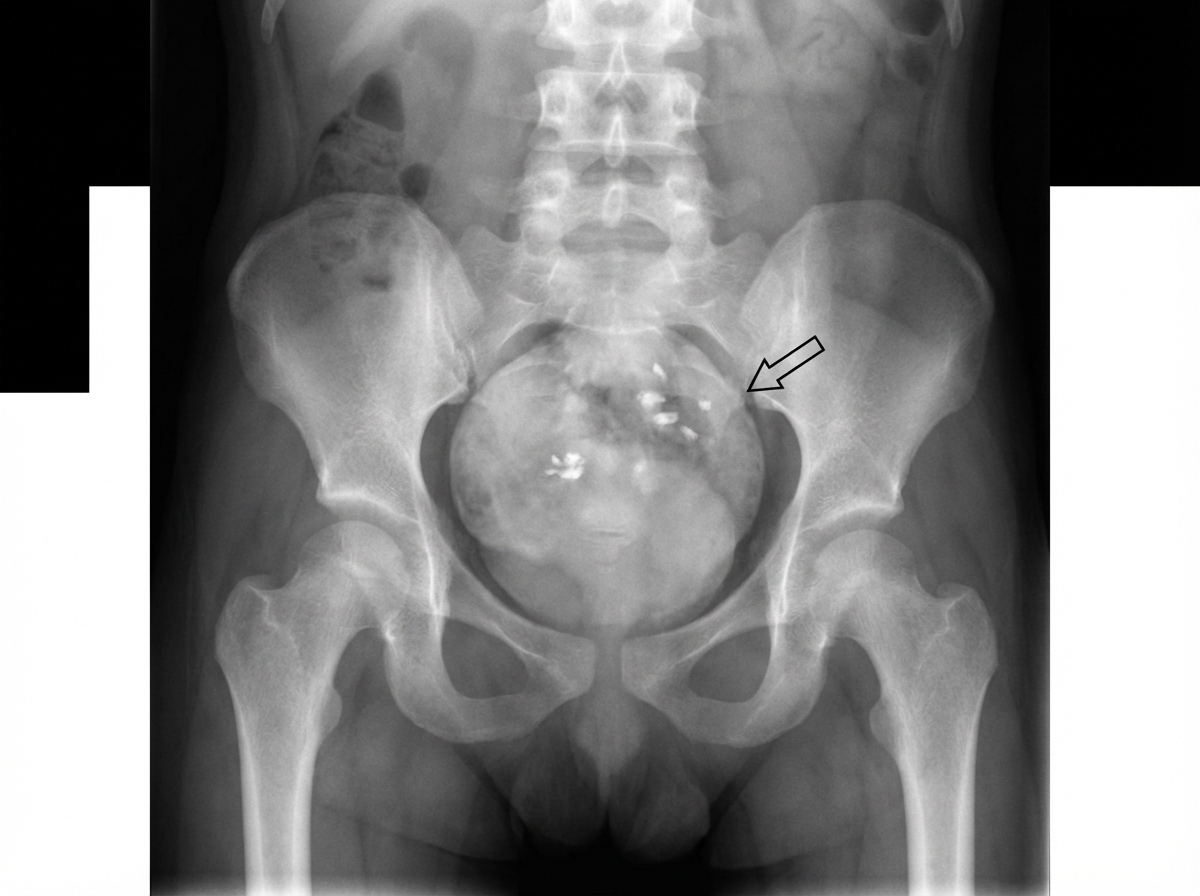

Explanation: ***Sacrococcygeal teratoma*** - Appears on **infantogram** as a large **presacral soft tissue mass** with characteristic **calcifications** and mixed densities. - Most common **congenital tumor** in neonates, easily identified by its **posterior location** and **heterogeneous appearance** on plain radiographs. *Hemangioma* - Represents a **vascular malformation** that appears as soft tissue density without the discrete mass characteristics seen on infantogram. - Typically requires **contrast studies** or **MRI** for proper visualization, not readily apparent on plain film infantogram. *Myelomeningocele* - Shows as a **posterior spinal sac** containing **neural elements** and CSF, representing a **neural tube defect**. - Associated with **spina bifida** and **vertebral arch defects**, distinct from the presacral mass pattern of teratoma. *Arnold-Chiari malformation* - A **hindbrain anomaly** involving **cerebellar tonsillar herniation** through the foramen magnum. - Not visible on **plain film infantogram** and requires **MRI** or **CT** for diagnosis of this intracranial abnormality.